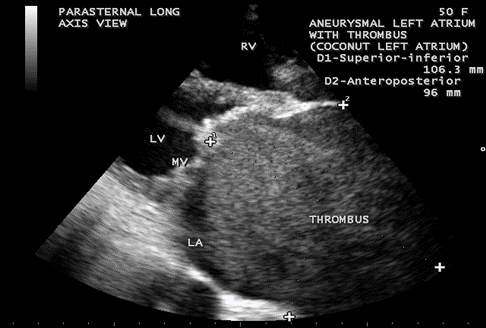

Case 5. Giant left atrium with dense SEC (spontaneous echo contrast) visible as massive thrombus occupying the entire giant left atrium and resembling as “coconut atrium” as shown in Figures 21 to 25 and movie in Figure 26

in rheumatic mitral stenosis in a 50- year old female. Patient was advised lifelong penicillin prophylaxis, Redo MVR (mitral valve replacement) and removal of thrombus with inverted T-shaped biatrial incision (endoatriectomy- transeptal superior approach)

Figure. 21. Parasternal long axis view showing the dense SEC (spontaneous echo contrast) visible as thrombus occupying the entire giant left atrium in a 50-year old female.

Figure 22. Tilted apical view showing the thrombus occupying the entire Left atrium in a 50-year old female.

Massive calcification of left atrium, predominantly affects the woman (74%) and it tooks an average duration of 19.7 years (17-20 years) to become manifest in rheumatic mitral stenosis and resembled a coconut shell [72]. The term ‘coconut atrium’ is misnomer to describe this condition and a complete opacification of giant left atrium with dense SEC seen as thrombus as shown in Figure 24, resembling a ‘coconut’ as in Figure 25 and this condition is better termed as ‘coconut atrium’ appropriately.